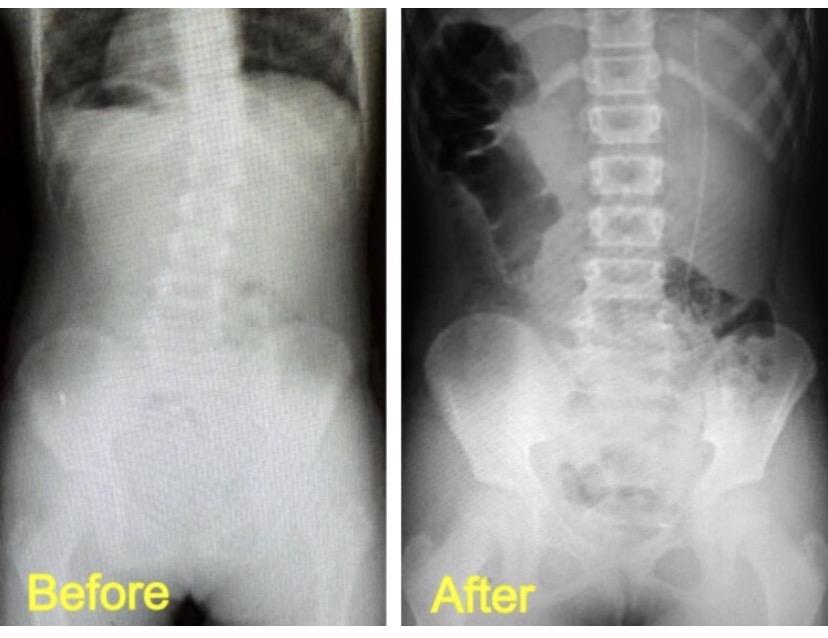

中〜高校生の改善例(女の子)

病院では「定期的な経過観察が必要」と言われ、ただただ経過観察をしていく中で、「他に何かできることはないのか…」「進行度合いの確認だけでなく根本的に改善させるような方法はないのか…」との親御様の切なる思いからインターネットで検索され当院に来院されました。現在も尚、病院でのリハビリ指導と当院でのカイロプラクティックケアに運動指導などを行いながら、さらなる改善へ向けて取り組まれています。

※これは個人の感想と画像の結果であり施術の効果を保障するものではありません。また効果には個人差があります。